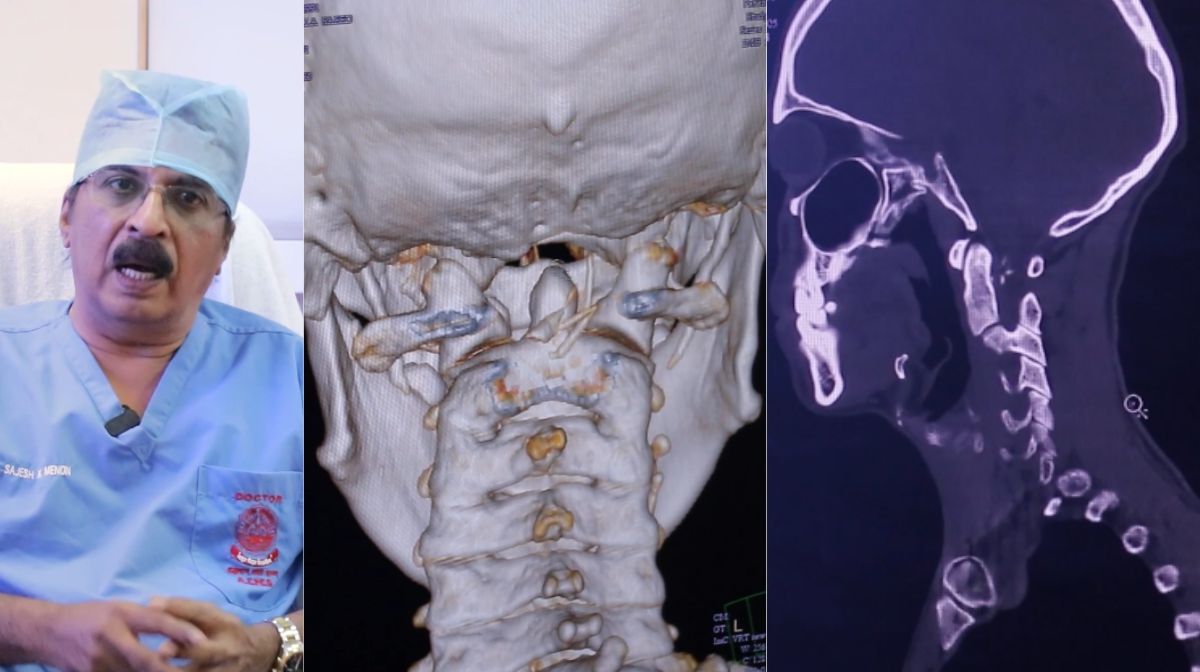

കഴുത്തിൻ്റെ പിറകിൽ മത്സ്യത്തിന്റെ പല്ല് സുഷുമ്നാ നാഡിയിൽ തറച്ചതിനാൽ യുവാവിന്റെ ഇടതുകയ്യും കാലും തളർന്ന അവസ്ഥയിലായിരുന്നു. തുടർന്ന് നടത്തിയ വിദഗ്ധ പരിശോധനയിൽ കഴുത്തിലെ സുഷുമ്നാ നാഡിയിൽ മത്സ്യത്തിൻ്റെ പല്ലിൻ്റെ പത്തിലധികം ഭാഗങ്ങൾ തറച്ചതായും കണ്ടെത്തി. ഉടനെ യുവാവിനെ വിദഗ്ധസംഘം ശസ്ത്രക്രിയയ്ക്ക് വിധേയമാക്കി. സുഷ്മന നാഡിയിൽ തറച്ച മത്സ്യത്തിൻ്റെ പല്ലുകൾ അടക്കമുള്ള ഭാഗങ്ങൾ നീക്കം ചെയ്യുകയും ചെയ്തു. യുവാവ് ആരോഗ്യം വീണ്ടെടുത്തു.